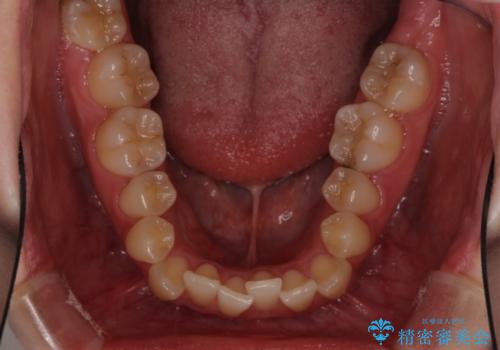

- 前歯のデコボコとクロスバイトを治したいとのことで来院された患者様です。

上下顎ともに歯列全体の側方拡大とIPR(歯と歯の間を削る)によってデコボコとクロスバイトが解消するように設計し、インビザラインにより治療を行うこととしました。

下顎骨の左側への骨格的なずれが強く、上下の正中の位置合わせや奥歯の咬み合わせ構築に苦労しました。